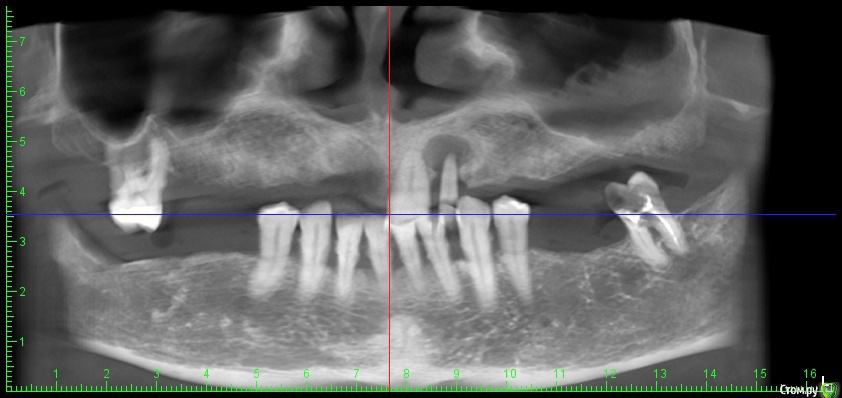

DenisV Опубликовано 11 декабря, 2017 Поделиться Опубликовано 11 декабря, 2017 Доктора, пациент обратился с целью установки имплантатов. На клКТ обнаружено затенение пазухи, отправлен к ЛОР на консультацию. Что это? синусит? ретенционка? Ссылка на комментарий

Большой Зеленый Опубликовано 12 декабря, 2017 Поделиться Опубликовано 12 декабря, 2017 Гайморит . 5 Ссылка на комментарий

Paganini Опубликовано 12 декабря, 2017 Поделиться Опубликовано 12 декабря, 2017 (изменено) Это синусит. И жалоб нет? Изменено 12 декабря, 2017 пользователем Paganini Ссылка на комментарий

колесников Опубликовано 12 декабря, 2017 Поделиться Опубликовано 12 декабря, 2017 Пузырьки газа в жидкости. Ссылка на комментарий